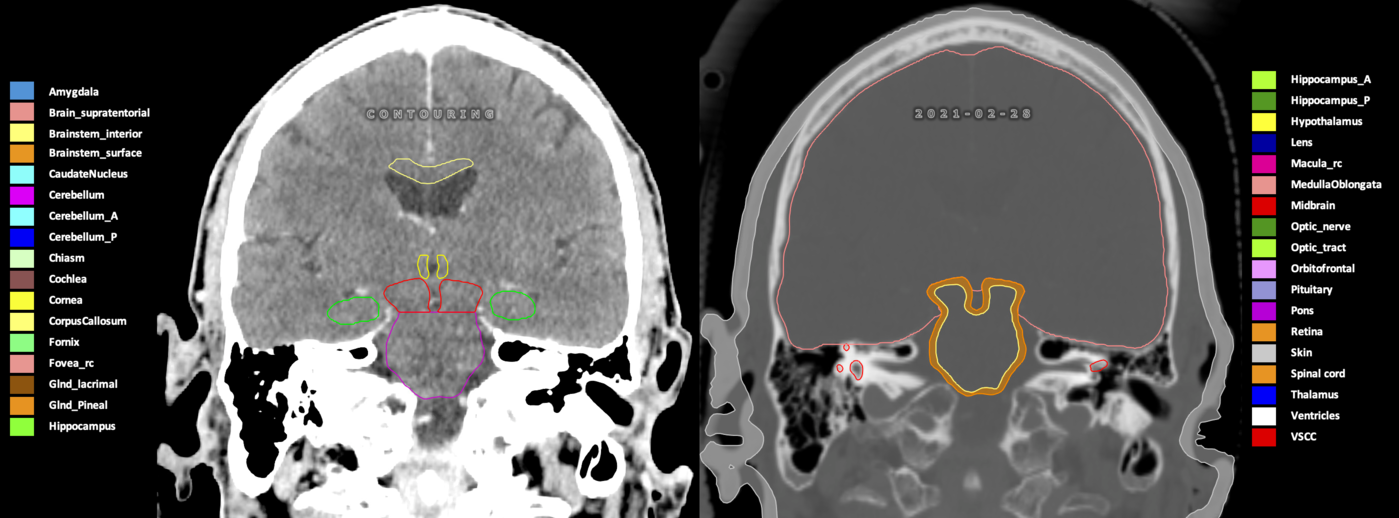

Eekers et al. have published an international neurological atlas for contouring of organs at risk in consensus with the European Particle Therapy Network (EPTN) in 2018 and an update in 2021. The purpose of this consensus atlas is to decrease inter- and intra-observer variability in delineating OARs relevant for neuro-oncology.

Included are all OARs known to be relevant for radiation-induced toxicity in neuro-oncology: brain, brainstem (midbrain, pons, medulla oblongata), chiasm, cerebellum (anterior & posterior), cochlea, cornea, hippocampus (anterior & posterior), hypothalamus, lens, lacrimal gland, optic nerve, pituitary, skin, and vestibular & semicircular canals. To further facilitate research on cognition, vision and radiological changes after irradiation of the brain, potential clinically-relevant OARs are included: amygdala, caudate nucleus, cerebellum (anterior & posterior), corpus callosum, fornix, macula, optic tract, orbitofrontal cortex, periventricular space (PVS), pineal gland, and thalamus.

Three-dimensional delineation of the 25 consensus OARs for neuro-oncology are shown on CT (WW/WL 120/40, 3000/600), 3T MR images, (T1Gd, T2FLAIR 1mm) and 7T MR (MP2RAGE 0.7 mm). All are presented in transversal, sagittal and coronal view.